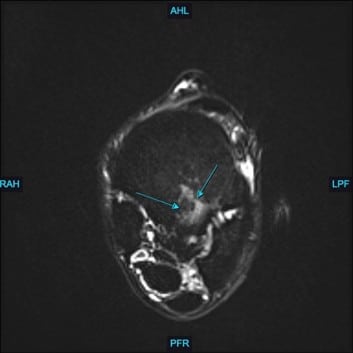

At Animal Imaging, Hugo was placed under general anesthesia and multiplanar MR images were acquired. The gelding was found to have moderate to marked, ill-defined fiber disruption of the origin of the proximal suspensory ligament with marked subchondral and endosteal sclerosis of proximal plantar third metatarsal. The proximal and body of the suspensory ligament was generally enlarged and rounded. The gelding also had marked subchondral sclerosis of dorsal central and third tarsal bones. Numerous, small cortical and subchondral cystic lesions of the dorsal distal intertarsal and tarsometatarsal joints.

Hugo was diagnosed with subchondral bone injury of third metatarsal bone with concurrent marked enthesitis and desmopathy of the origin of the proximal suspensory ligament. The gelding also had moderate to marked chronic desmopathy of the proximal suspensory ligament and body and Moderate to marked distal intertarsal and tarsometatarsal osteoarthropathy.